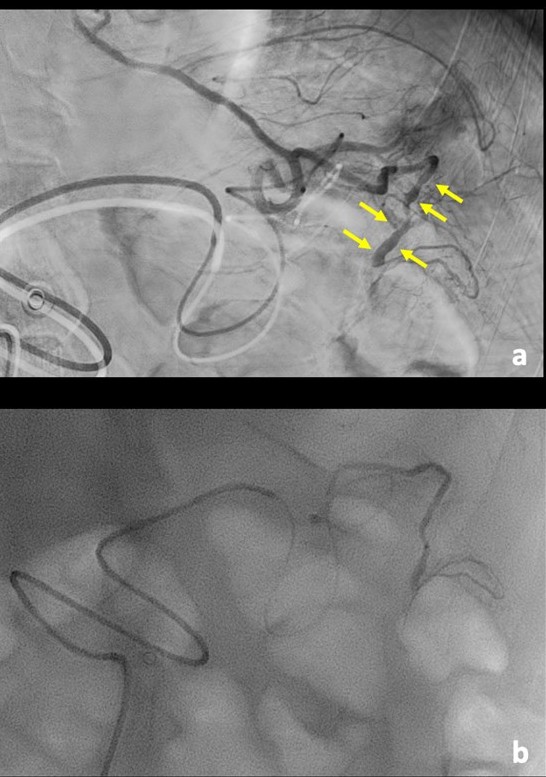

The diagnosis of ruptured aneurysm was suspected and an arteriography was performed, which showed ectatic and anomalous branches of the left gastroepiploic artery associated with mesenteric hemorrhage. The affected artery was successfully embolized with ethylene vinyl alcohol copolymer, a liquid embolic agent. Hemoglobin remained stable in the early post-embolization period. The patient was discharged on the third day after the procedure.(Fig. 2)

Figure 2: Digital subtraction angiography (a), showing an ectatic and irregular left gastroepiploic artery (arrow). Because the angiography was performed with a day delay from the CT, the biggest aneurysmal sac is no longer seen, as it already thrombosed. Nevertheless, we decided to embolize (b) with liquid embolic (Squid®) the remaining abnormal artery, to prevent further complication.